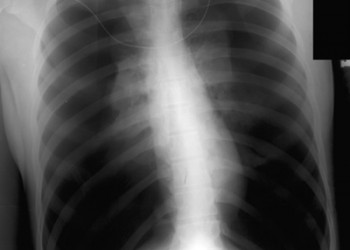

La nou-născut, silueta cardiacă reprezintă circa 1/3 din lățimea toracelui. Ce facem când vedem o radiografie cum este cea din imagine la un adult?

Nu este vorba despre o malformație, ci despre un cord tubular, cel mai adesea în cadrul unei patologii pleuro-pulmonare. Acest aspect apare atunci când diametrul maxim orizontal al cordului este sub 11 cm sau indicele cardio-toracic (raportul dintre diametrul cardiac transvers maxim şi diametrul toracic transvers maxim) este sub 1/3.

Cordul tubular poate fi întâlnit în BPOC cu emfizem sever, astm bronșic, alte sindroame de hiperinflație pulmonară, pneumotorax bilateral sau obstrucție de bronhii principale (cu colabarea plămânului în hil) și în unele cauze de insuficiență adrenală (boala Addison), datorită hipovolemiei cronice și încărcării volemice scăzute a aparatului cardiocirculator.

În cazul bolilor pulmonare obstructive, consecința acestei “înghesuiri” a cordului de către plămânul hiperinflat este umplerea deficitară a ventriculului stâng, disfuncție diastolică și debit cardiac scăzut.